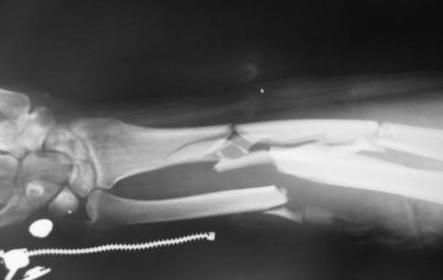

Больной Б. 43 лет, находится в клинике с диагнозом: Автотравма от

17.12.08 г. Открытый (3а) оскольчатый чрезмыщелковый перелом левой

плечевой кости, закрытые оскольчатые переломы диафизов костей левого

предплечья.

признаков воспаления. Планируется сначала выполнить остеосинтез

локтевой кости пластиной DCP, затем остеосинтез плечевой кости по

внутренней поверхности пластиной, по наружной - винтами, после

остеосинтез лучевой кости LCP пластиной. Какие альтернативные методы

лечения возможны в данной ситуации?